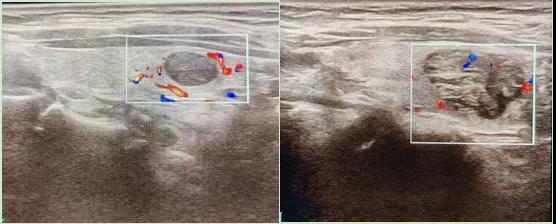

二、彩超如何“揪出”甲狀腺瘤?

彩超是一種無創(chuàng)、無輻射的檢查手段,被譽為甲狀腺的“高清攝像頭”。它的原理是:

超聲波探測:通過發(fā)射高頻聲波,生成甲狀腺的實時圖像。

彩色血流顯示:用紅藍色標記血流信號,區(qū)分腫瘤的供血情況。

1.形態(tài):良性多呈圓形,邊界清晰;惡性可能不規(guī)則、邊緣模糊。

2.回聲:低回聲結(jié)節(jié)風(fēng)險較高(像“烏云”一樣暗)。

3.鈣化:細小砂礫樣鈣化提示惡性可能。

4.血流信號:惡性結(jié)節(jié)常有豐富紊亂的血流。